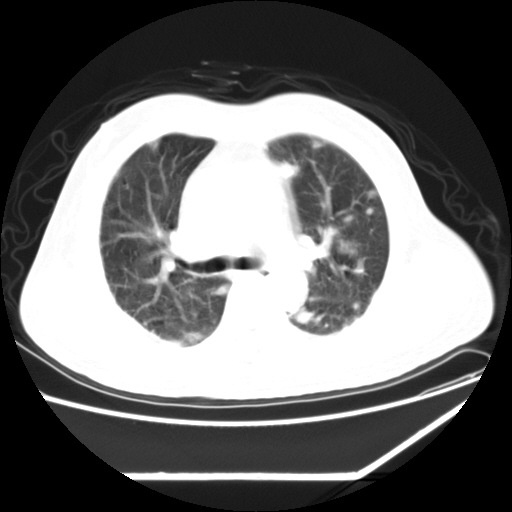

男,57,畏寒,发热

双侧亚急性血型播散性肺结核

双侧胸膜结核

两侧多发肺脓肿,两侧胸膜增厚,抗炎治疗后复查

两肺野多发大小不一高密度灶,纵膈内见肿大淋巴结,要考虑转移瘤可能。双侧胸腔少量积液。

双肺多发结节样病灶,部分内见透光区,纵隔内见淋巴结肿大。结核临床如有畏寒,高热,白细胞增高首先考虑迁徙性肺脓肿(多是金黄色葡萄球菌感染)。

注意除外转移瘤。

1)考虑两肺感染性病变(金黄色葡萄球菌肺炎?);建议抗炎治疗后复查排除其他。2)双侧少量胸腔积液。

双肺典型的亚急性粟粒性肺结核